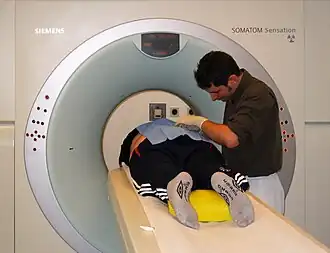

Спиральная компьютерная томография

Спиральная КТ используется в клинической практике с 1988 года, когда компания «Siemens Medical Solutions» представила первый спиральный компьютерный томограф. Спиральное сканирование заключается в одновременном выполнении двух действий: непрерывного вращения источника — рентгеновской трубки, генерирующей излучение, вокруг тела пациента, и непрерывного поступательного движения стола с пациентом вдоль продольной оси сканирования z через апертуру гентри. В этом случае траектория движения рентгеновской трубки относительно оси z (направления движения стола с телом пациента) примет форму спирали.